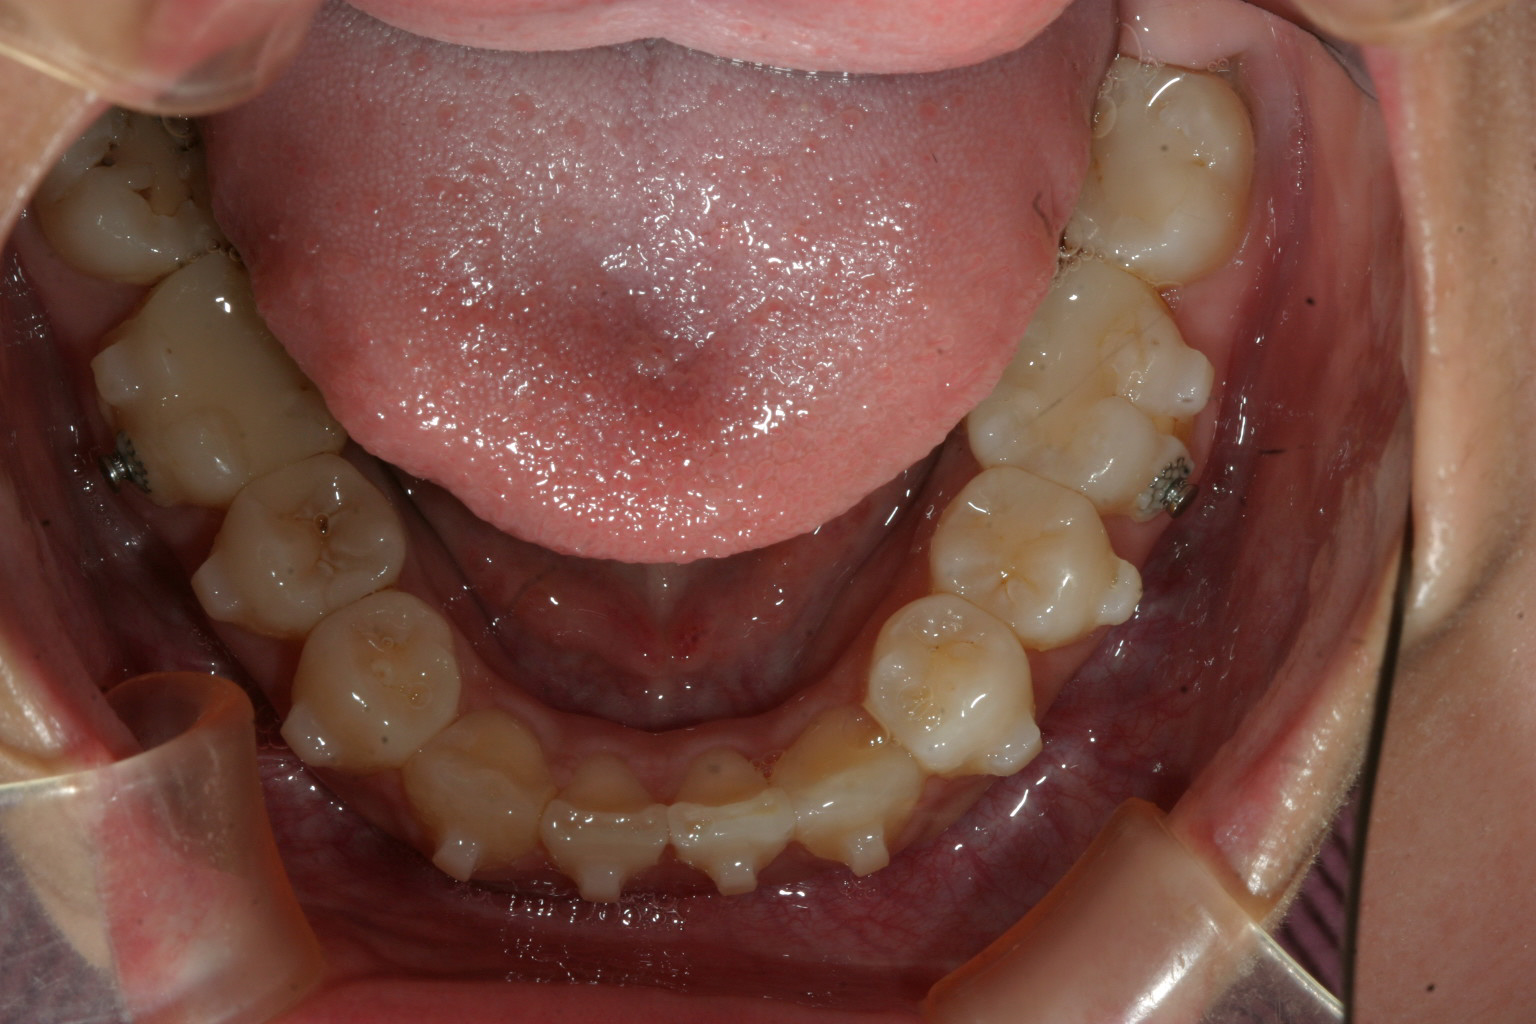

下顎もアタッチメントも取れ綺麗に改善しました。

オーバージェット感もバッチリです。

正中もビシッと合って綺麗に改善してます。